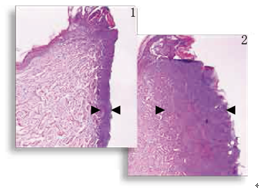

圖1,2

減輕熱損傷 組織學(xué)顯示,對(duì)比標(biāo)準(zhǔn)的電切尖端切口(圖2 ),表觀切口(圖1)明顯熱損傷減少